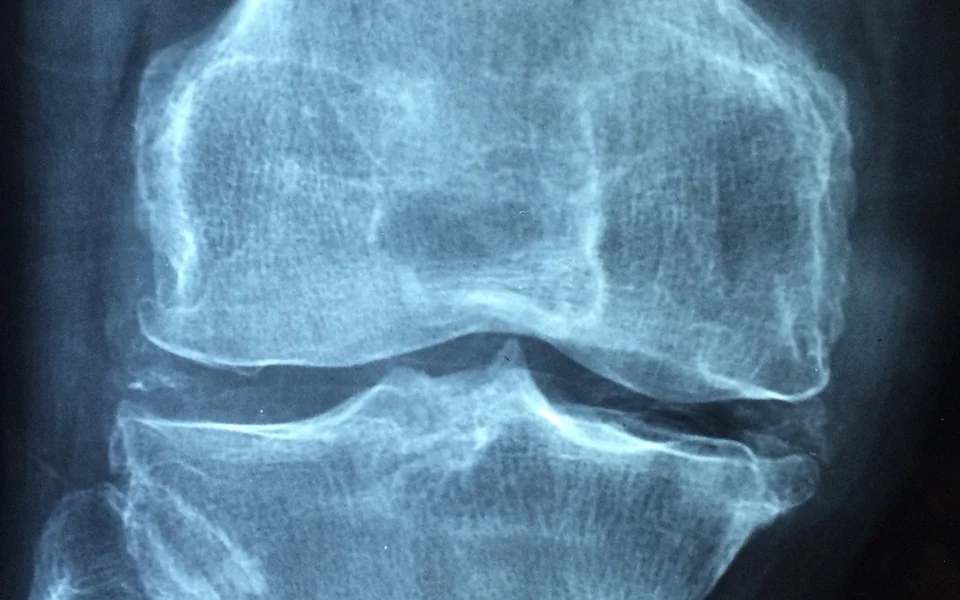

염증성 장질환의 진단은 주로 환자의 증상과 병력을 바탕으로 이루어집니다. 의사는 환자의 증상에 대한 상세한 정보를 수집한 후, 필요에 따라 다양한 검사를 시행합니다. 다음은 일반적으로 수행되는 진단 방법입니다:

• 영상 검사 (CT, MRI 등)